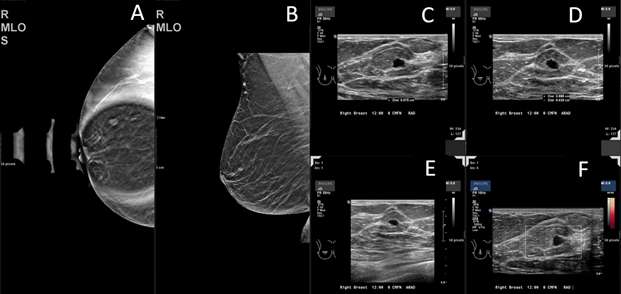

Breast metastasis from melanoma to an intramammary lymph node 5 years after the initial tumor was identified:

Case 3: